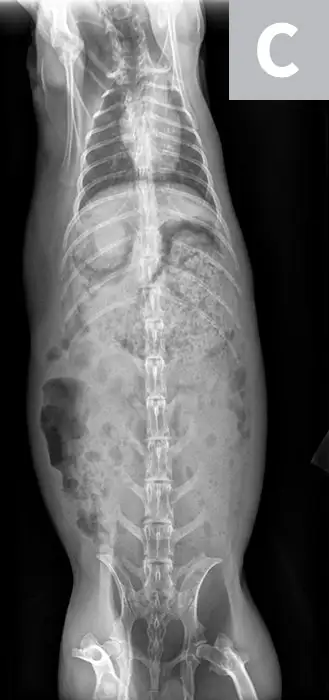

Victor was sedated with midazolam (0.5 mg/kg IM) to reduce stress during IV catheter placement and diagnostic testing. Abdominal radiographs (Figure 2) showed heterogeneous material in the stomach, which was inappropriately large for an anorexic rabbit; no obstructive pattern was seen.

FIGURE 2A

Abdominal and partial thoracic radiograph, left lateral view (A); abdominal and partial thoracic radiograph, right lateral view (B); and abdominal and thoracic radiograph, ventrodorsal view (C) showing heterogeneous material in the stomach but no obstructive pattern